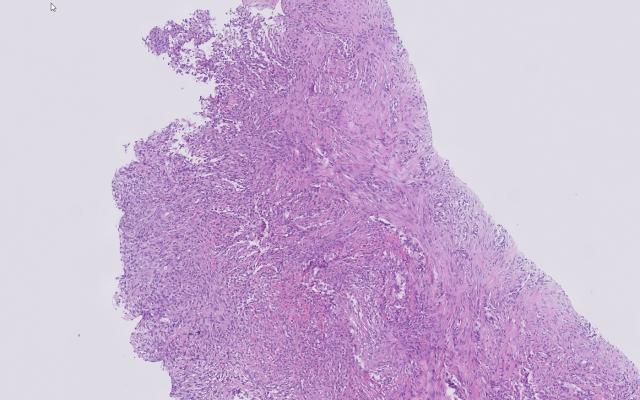

Een 72-jarige man zonder relevante voorgeschiedenis en zonder medicatiegebruik onderging een coronaire angiografie (CAG) vanwege angineuze klachten. De procedure werd uitgevoerd via de rechter a. radialis en verliep ongecompliceerd. Er werden geen stenosen gezien. Een dag na de procedure ontstond rond het middaguur een zwelling aan de rechterzijde van zijn hals. Deze zwelling nam gedurende ongeveer twee uur toe in omvang en stabiliseerde daarna spontaan. De zwelling was uitwendig zichtbaar (figuur a), en bij palpatie zacht elastisch, zonder pulsaties. De zwelling veroorzaakte geen kortademigheid maar wel pijn bij het slikken. De patiënt had geen trauma doorgemaakt. De huisarts beoordeelde…